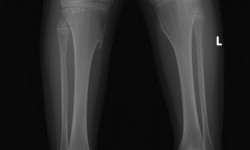

METAPHYSEAL CHONDRODYSPLASIA (Schmidt Type)

By Admin | September 12, 2013 - 2:48 pm | Musculoskeletal, Skeletal Dysplasias

Case.1

Case2. Fig.1

Case2. Fig.2